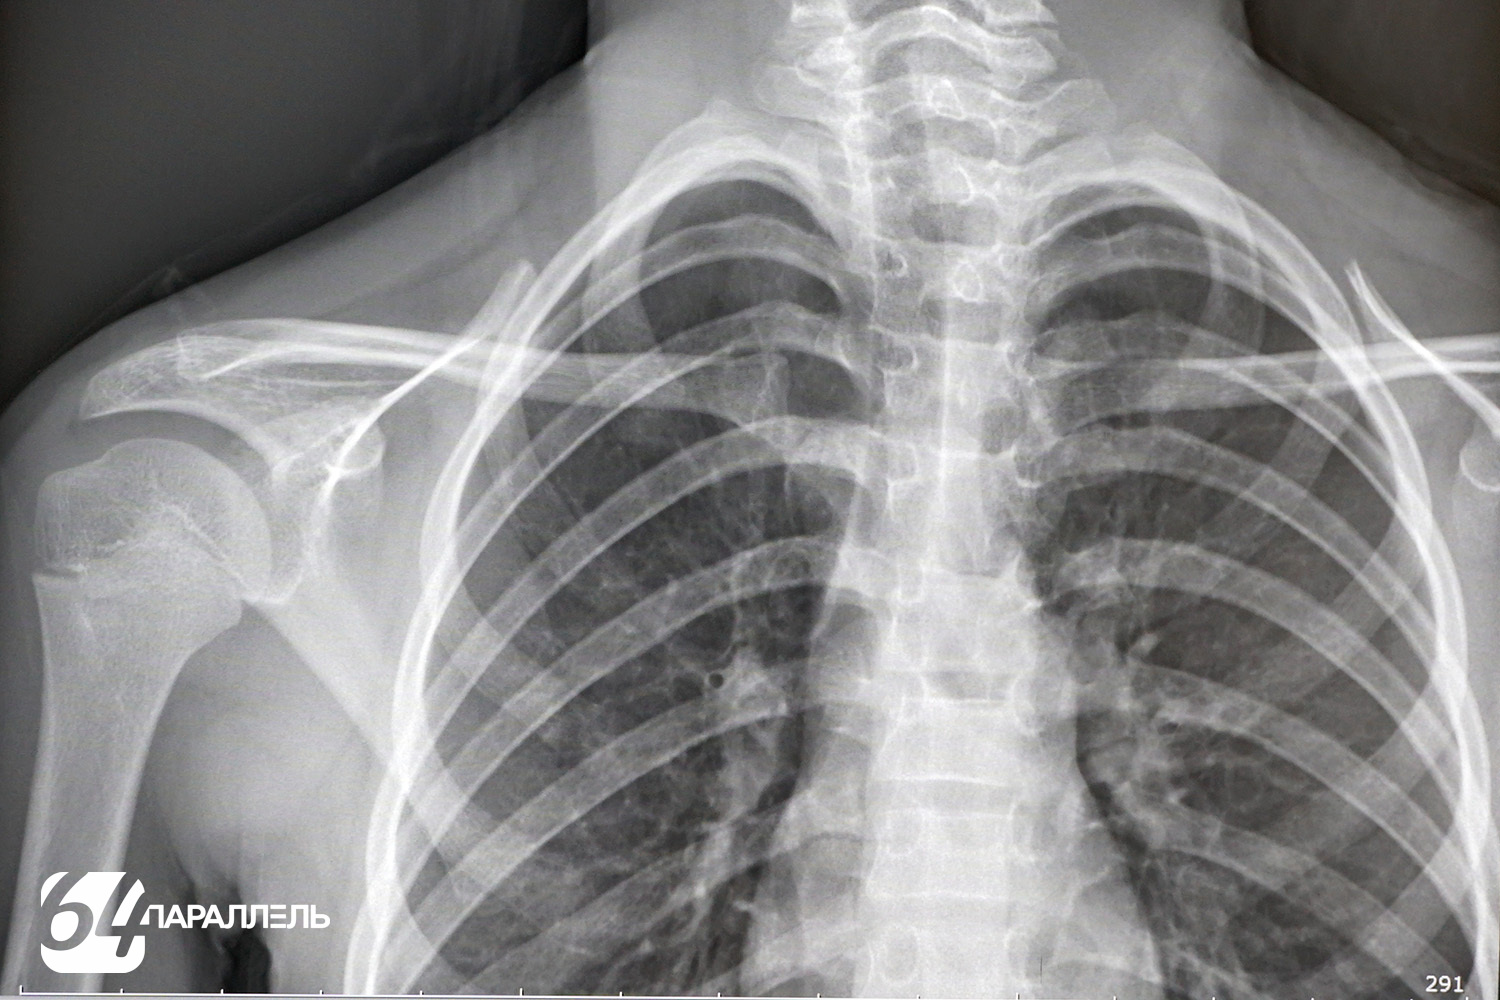

У нового аппарата множество преимуществ. Так, теперь получают качественные цифровые снимки с обширной постпроцессинговой обработкой: их можно увеличивать, уменьшать, менять яркость и контрастность, детально рассматривать зону интереса, что невозможно было сделать на аналоговых снимках. Также аппарат позволяет выполнять полипозиционные исследования, при этом не нужно менять положение пациента. Таким образом можно из разных точек заглянуть «внутрь» человека, не двигая его. Это особенно важно для маломобильных и тяжёлых пациентов. На трубке аппарата установлена видеокамера, которая передает изображение на консоль оператора, и пациент всё время находится на виду.

– Надо понимать, что, несмотря на все преимущества Opera Swing – это всё-таки рентген-аппарат с соответствующими возможностями и пределами метода. Он не заменит ни МСКТ, ни МРТ, так как даёт плоскостное изображение трехмёрного объекта, но не более. Огромное спасибо компании «Северсталь» и фонду «Доброта Севера» за такой подарок нашей больнице, – продолжает Юлия Лушина.